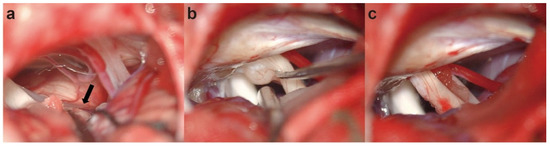

Background: Most cases of hemifacial spasm result from mechanical compression at the root exit zone of the facial nerve by vascular loops, and only a few cases are caused by vestibular schwannoma. Case presentation: We report a case of symptomatic hemifacial spasm induced [...] Read more.

Background: Most cases of hemifacial spasm result from mechanical compression at the root exit zone of the facial nerve by vascular loops, and only a few cases are caused by vestibular schwannoma. Case presentation: We report a case of symptomatic hemifacial spasm induced by a small vestibular schwannoma that was totally resected. A 64-year-old man was admitted to our department with a 14-month history of symptomatic right-sided hemifacial spasm. During the process of microvascular decompression, no definite vessel was found to compress the facial nerve. By further exploration of regions other than root exit zone, a small vestibular schwannoma compressing the internal auditory canal portion of facial nerve from the ventral side was discovered. Resection of the tumor was then conducted. The symptoms of hemifacial spasm disappeared immediately after surgery. Conclusions: We should be aware that magnetic resonance imaging is not always precise and perhaps misses some miniature lesions due to present image technique limitations. A small vestibular schwannoma might be the reason for HFS, although preoperative magnetic resonance tomography angiography showed possible vascular compression at the facial nerve root. More importantly, a full-length exploration of the facial nerve is in urgent need to find potential compression while performing microvascular decompression for HFS patients. Full article

(This article belongs to the Section Neurosurgery and Neuroanatomy)

Show Figures

Figure 1